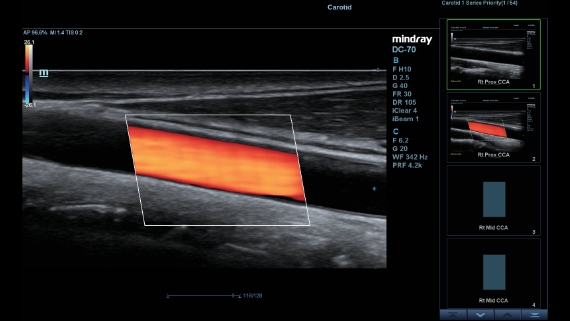

Klinische Bilder

Schallk?pfe